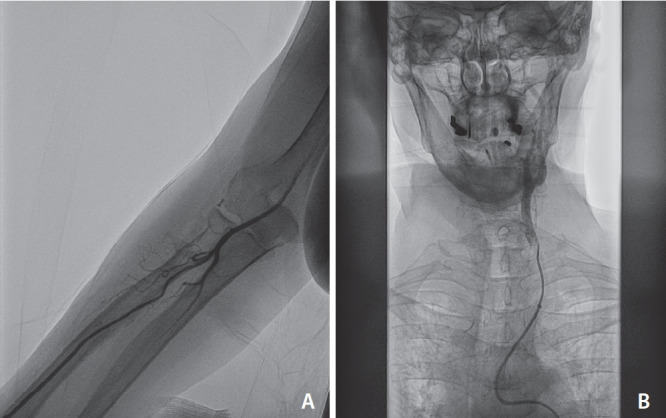

Results: Of 20 patients selected, 10 (50%) had occlusion of M1 segment of middle cerebral artery (MCA), 6 (30%) of internal carotid artery (ICA) terminus, and 4 (20%) with M2 MCA occlusions; 12/20 (60%) were right-sided occlusions and 8/20 (40%) were left-sided. The mean National Institutes of Health Stroke Scale score was 9.25 at admission. Successful revascularization to mTICI 2b-3 was achieved in 18/20 patients (90%). Intracranial complications were reported in 2 (10%) patients. Rate of radial artery occlusion at 24 hours was 10,6%; no access-site haemorrhagic complications were reported. Symptomatic intracranial hemorrhage occurred in 2 (10%) patients. mRS score 0-2 at 3 months was 50%.

Abstract Image